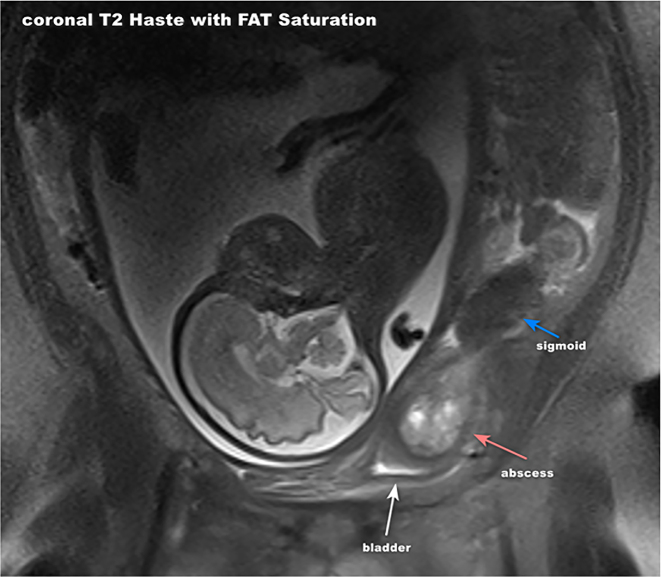

Case presentation: This paper presents a case of a 37-year-old multiparous woman diagnosed with complicated diverticulitis, including colovesical fistula and bladder abscess formation.